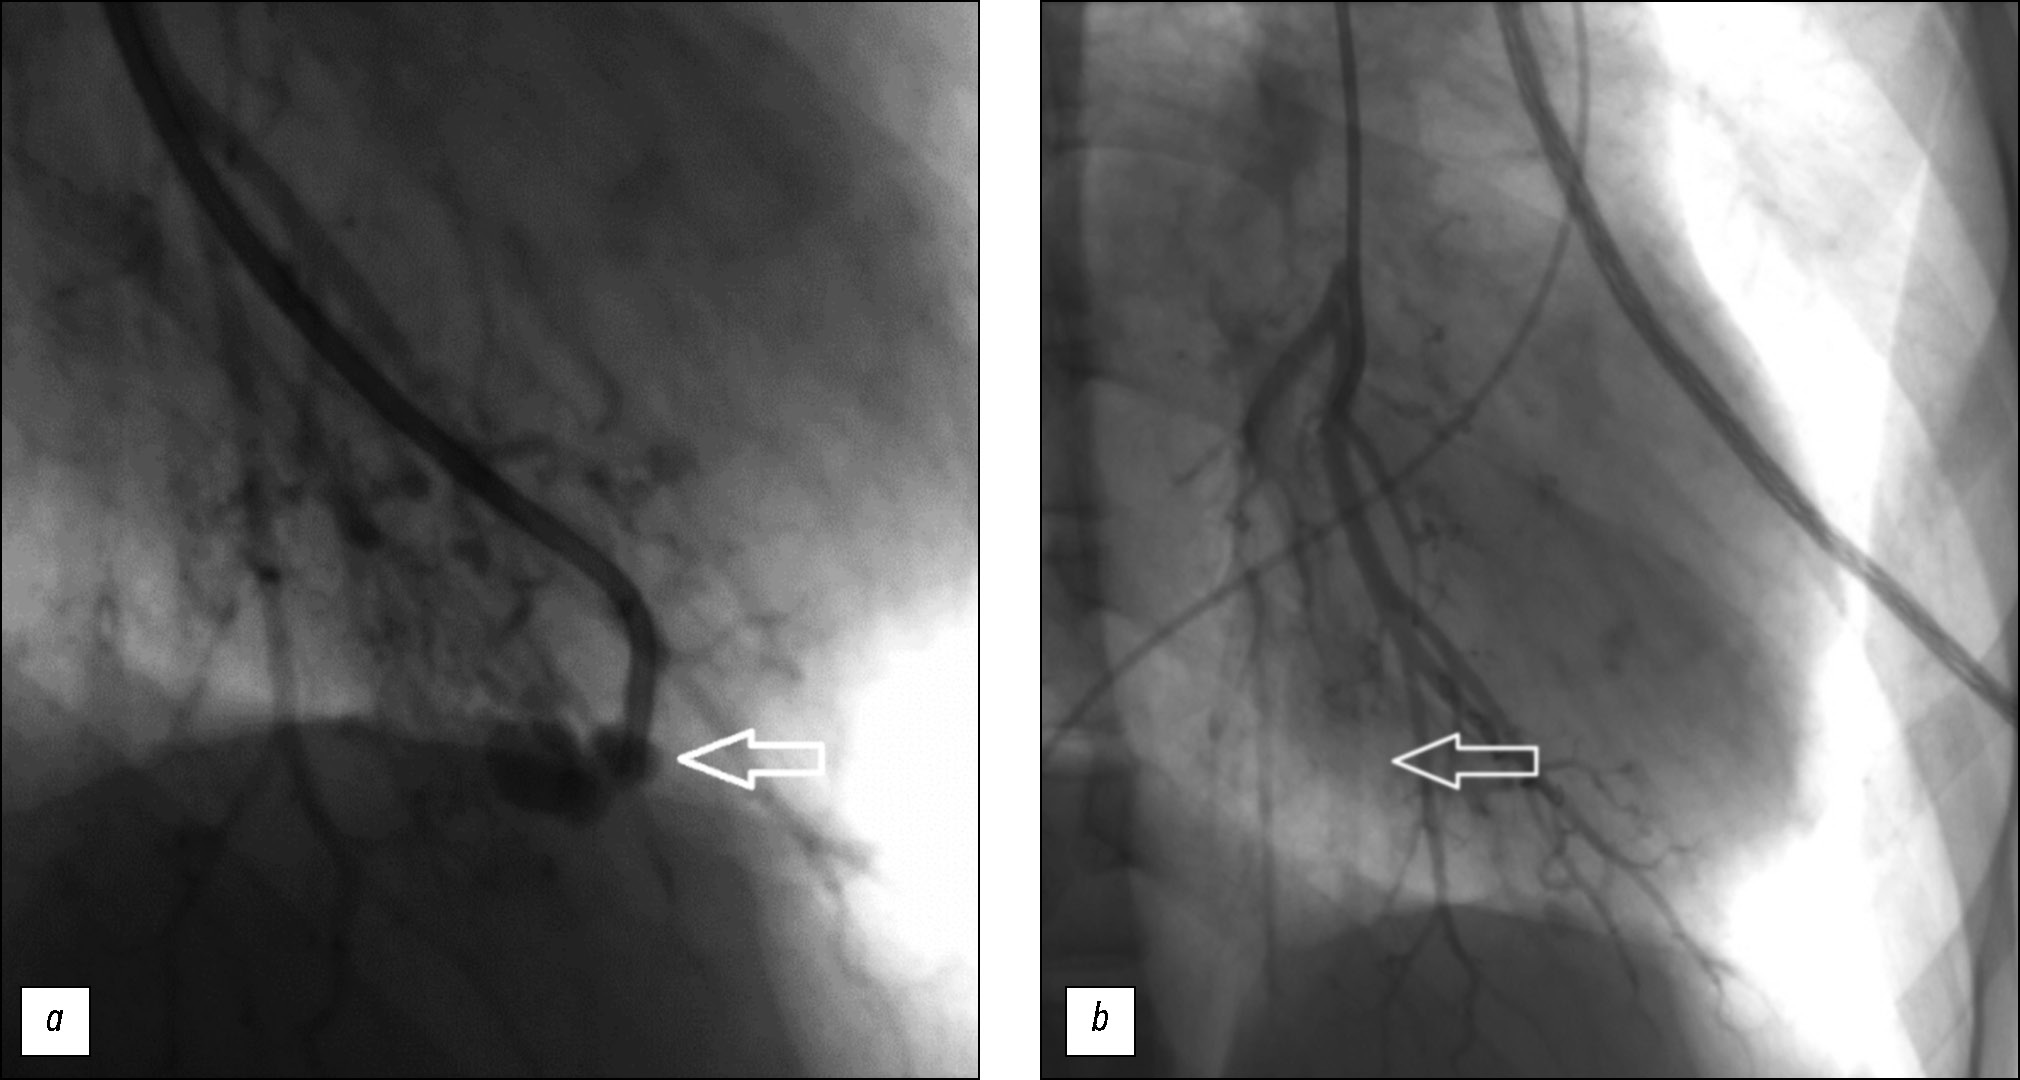

Вмешательство на лёгочной артерии подтвердило это нарушение (рис. 3, а). Аневризму эмболизировали с помощью спирали MReye размером 0,035 дюйма × 3 мм × 4 мм. Результаты контрольной ангиографии подтвердили успешность процедуры (рис. 3, b), осложнений не наблюдалось.

Рис. 3. Ангиография: a — ангиографический снимок в переднезадней проекции, в терминальной ветви VΙ сегмента обнаружено аневризматическое расширение размером 4,0×5,0 мм (обозначено белой стрелкой); b — контрольная ангиография в переднезадней проекции, эмболизационную спираль ввели через установленный катетер (обозначена белой стрелкой).